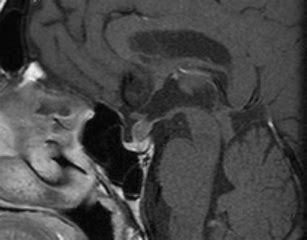

Q

enhancing and thickened hypothalmus

A

1. sarcoidosis

2. histiocytosis x

3. lymphoma

4. mets